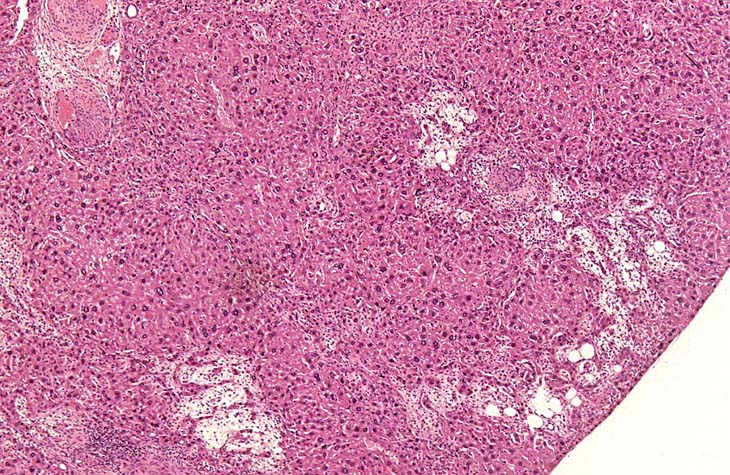

A relative discrete Ito cell tumor is present within this hepatic lobe; a higher magnification shows proliferation of stellate cells within the hepatic sinusoidal spaces.